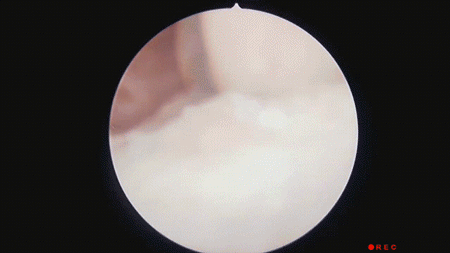

秋高气爽,恰是磨练好时节。但不少东谈主闲居缺少畅通,踝关节周围肌肉力量不及,无法灵验空隙关节,此时霎时进行高强度畅通,很容易崴脚。

崴脚后,千万别作念这些事❌

立即揉搓或热敷:可能会加重肿胀和出血。

强行手脚或赓续行走:易导致二次毁伤。

猖狂贴膏药或涂抹药油:可能会秘密症状,贻误治愈。

✅正确要道:

崴脚后的48-72小时内,可服从以下五原则。

1.暂时制动:别再手脚受伤的脚踝,立即罢手行走或畅通,扫视进一步毁伤。

2.相宜负重:在不疼的前提下,可稍稍手脚,幸免关节僵硬。

3.立时冰敷:用毛巾包好冰袋,别让冰袋径直斗争皮肤。每次冰敷15~20分钟,每2小时重迭一次。

4.加压包扎:用弹性绷带“8字缠绕”踝关节,松紧度以能伸进一根手指为宜。若脚趾发麻、皮肤发紫,要缩小绷带。

5.举高患肢:平躺时把脚垫高,最佳高于腹黑的位置。